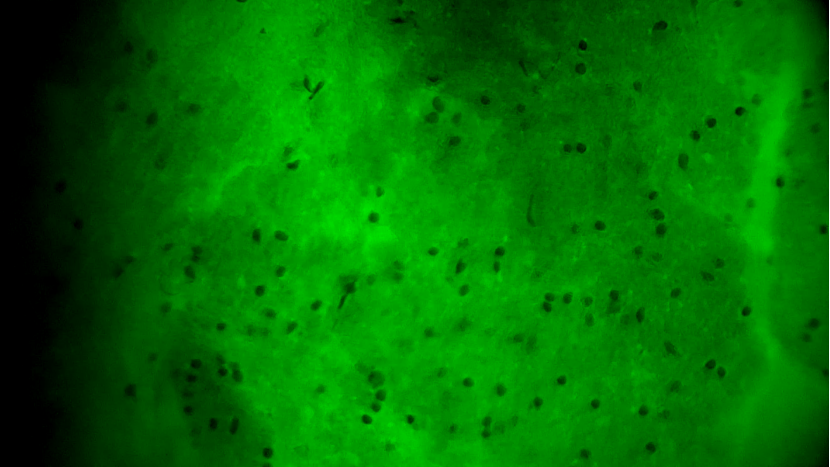

術(shù)中EndoSCell?細(xì)胞圖像如下:

腫瘤中心區(qū)域:細(xì)胞核異型性顯著,分布密集且不規(guī)則,陽(yáng)性。

腫瘤邊緣區(qū)域:個(gè)別細(xì)胞核存在異型性,密度下降,分布不規(guī)則,陽(yáng)性。

正常細(xì)胞組織:細(xì)胞核形態(tài)正常,分布均勻,陰性。